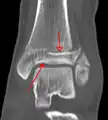

CT

CT scans may be indicated when there is concern for a highly comminuted fracture or a fracture involving the joint surface.[9] This imaging may be used for surgical planning.